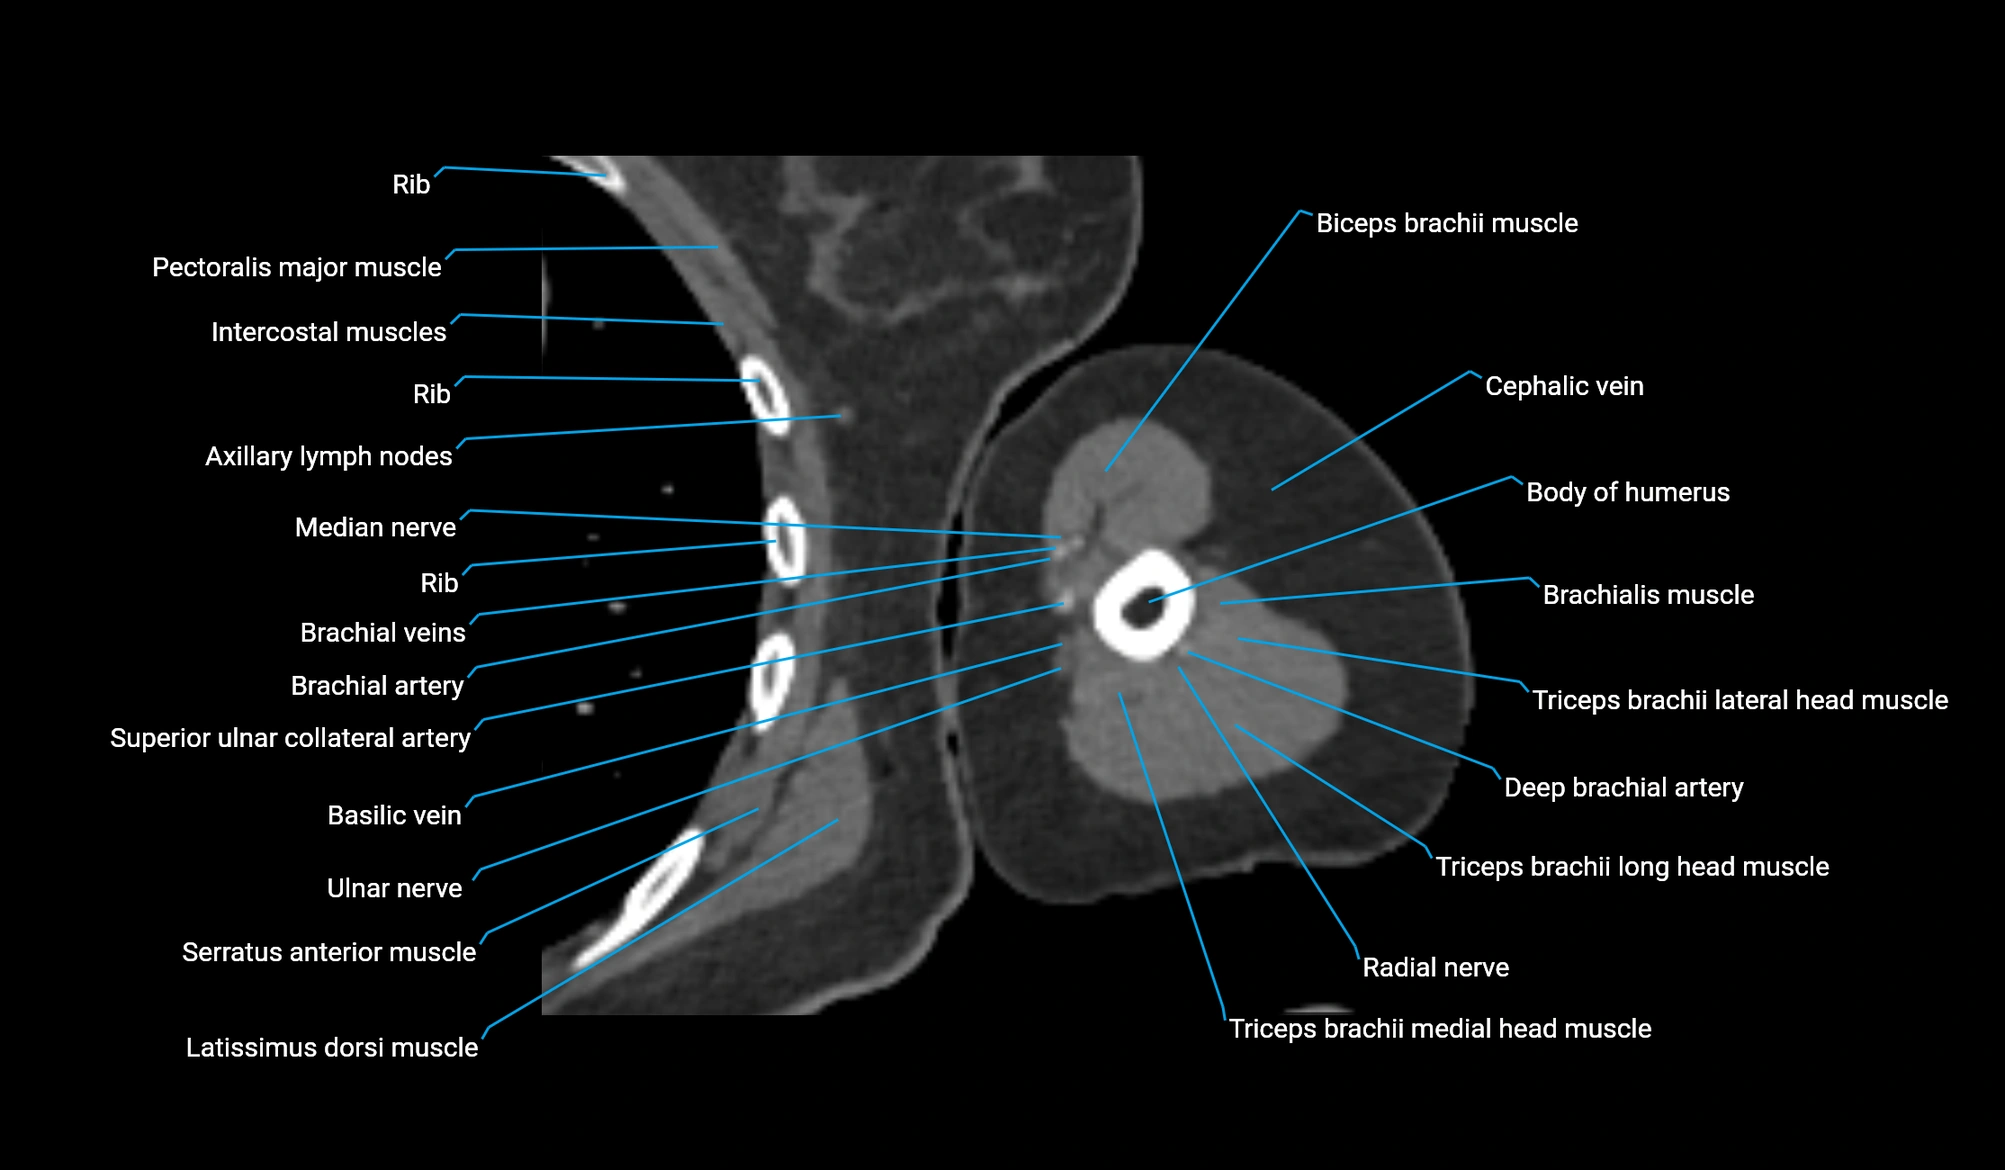

- Axillary lymph nodes

- Biceps brachii muscle

- Body of humerus

- Brachialis muscle

- Cephalic vein

- Deep brachial artery

- Lateral head of triceps brachii muscle

- Long head of triceps brachii muscle

- Medial head of triceps brachii muscle

- Median nerve

- Pectoralis major muscle

- Pectoralis minor muscle

- Radial nerve

- Superior ulnar collateral artery